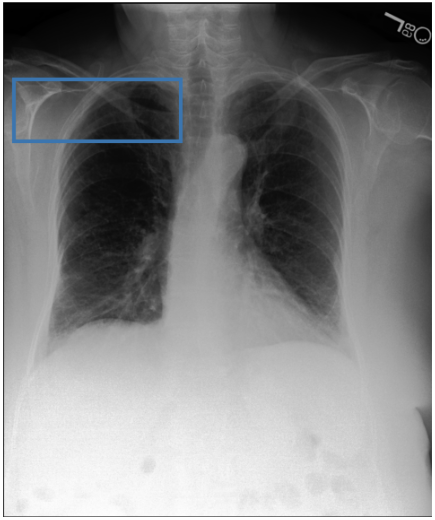

Figure 3 shows phrase grounding results for the phrase “Chronic inflammatory changes predominantly in both lung apices” on an image from PadChest-GR [11]. Both CURE and MAIRA-2 successfully identify the lung apices associated with the described findings. However, CURE’s localization is more accurate and better aligned with the phrase semantics, while MAIRA-2 provides a coarser prediction that only partially covers the relevant areas. As expected, MedGemma-4B-IT does not produce visual grounding outputs, and thus no bounding boxes are shown for this model.